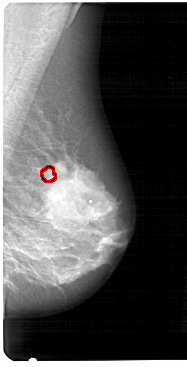

FILE: A_1270_1.RIGHT_MLO.OVERLAY

TOTAL_ABNORMALITIES 1

ABNORMALITY 1

LESION_TYPE CALCIFICATION TYPE PLEOMORPHIC DISTRIBUTION CLUSTERED

ASSESSMENT 4

SUBTLETY 4

PATHOLOGY BENIGN

TOTAL_OUTLINES 1

BOUNDARY